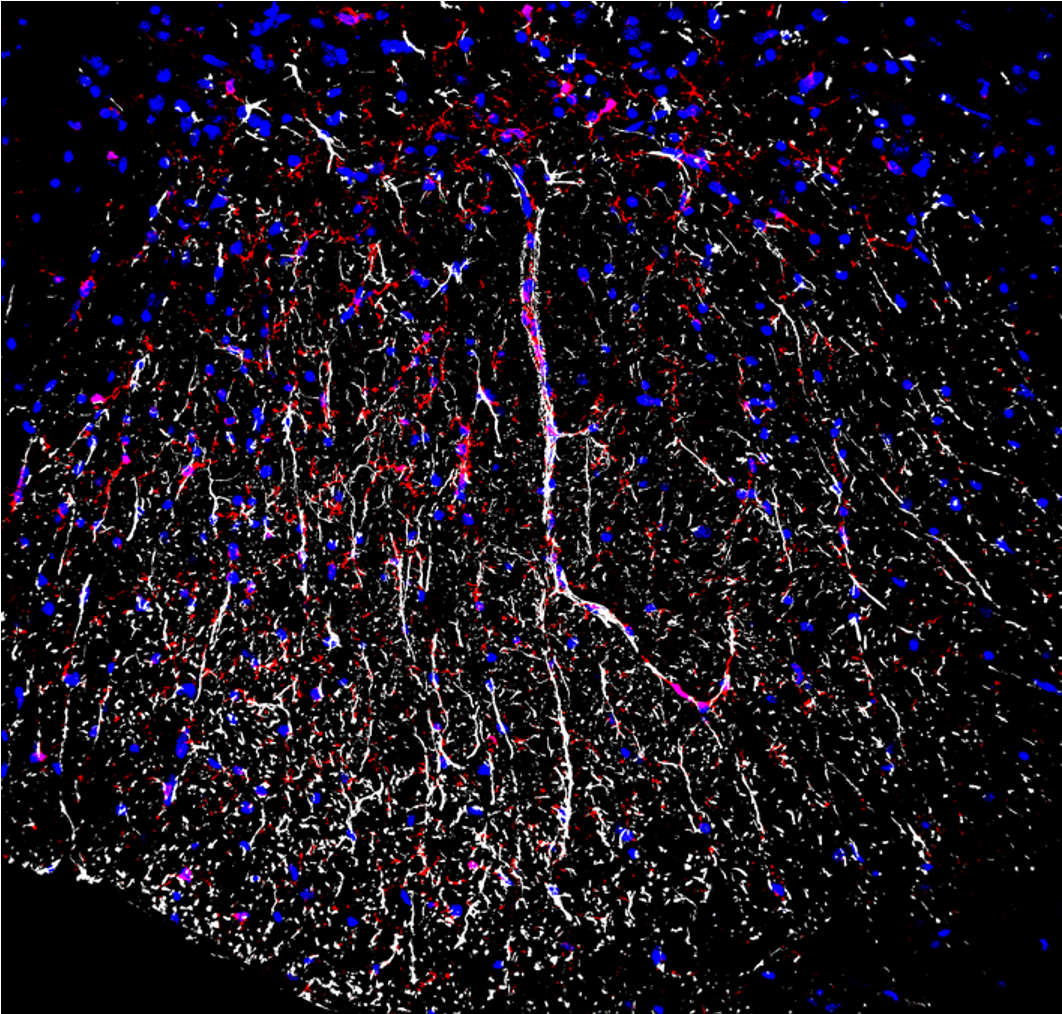

Striking Laboratory Data Images

Laboratory Data Gallery

Universe of the brain